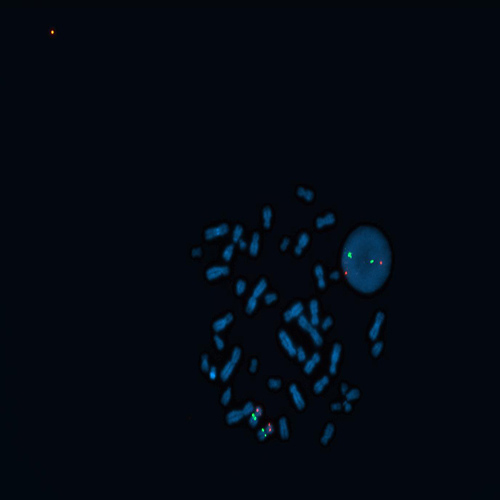

CDKN2A (9p21) / 9q21 hybridized to a metaphase spread showing a normal pattern (2R2G).

Hemizygous deletions and rearrangements of chromosome 9, band p21 are among the most frequent cytogenetic abnormalities detected in pediatric acute lymphoblastic leukemia (ALL). This deletion includes loss of the CDKN2A (previously known as p16, INK4A or MTS1) / CDKN2B (previously known as p15, INK4B or MTS2) genes, which are cell cycle kinase inhibitors and important in leukemogenesis. The CDKN2A (9p21) specific FISH probe is optimized to detect copy numbers of the CDKN2A gene region at region 9p21. The 9q21 region probe is included to facilitate chromosome identification.